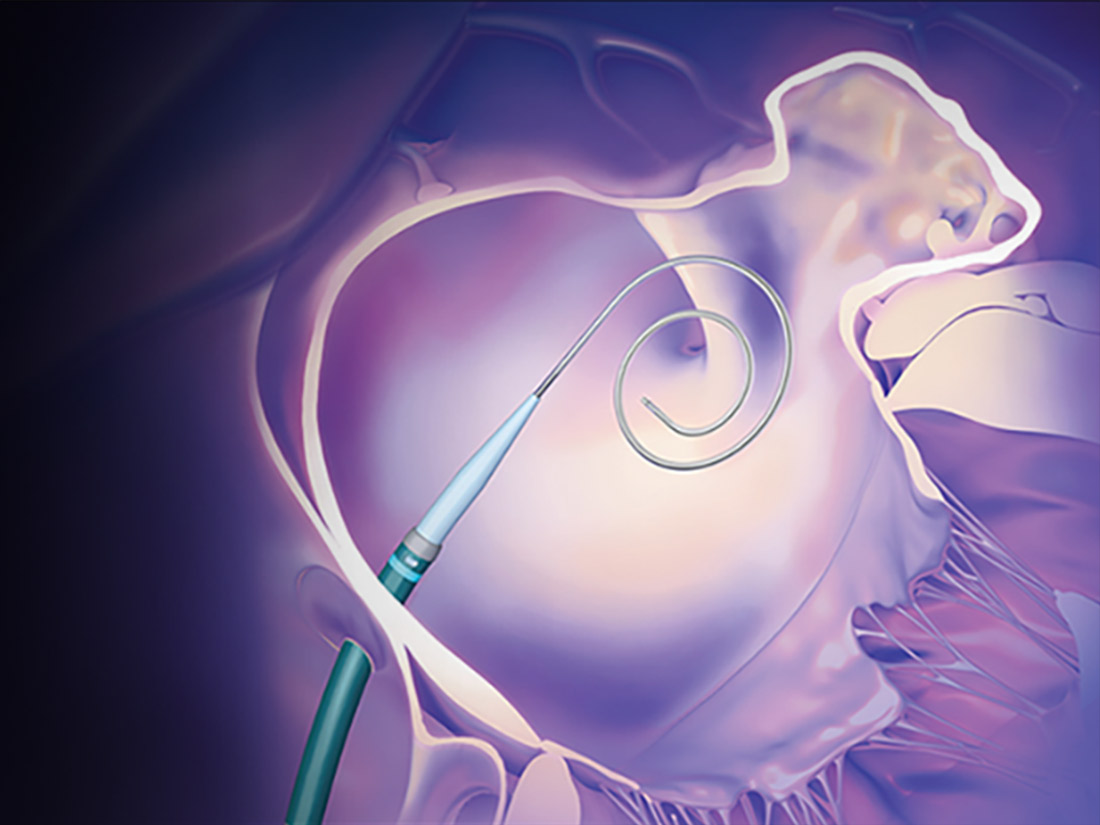

The VersaCross Connect LAAC Access Solution connects VersaCross™ technology with compatible WATCHMAN™ sheaths for zero exchange left heart access.

The VersaCross Connect LAAC Access Solution connects VersaCross technology with WATCHMAN* sheaths for zero exchange left heart access.

Discover how the 3-in-1 RF wire and transseptal dilator simplify left atrial appendage closure (LAAC) by connecting the VersaCross Connect Transseptal Dilator and WATCHMAN Access Sheath* for zero exchange left heart access